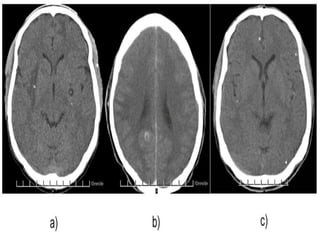

RT MCA infarct

Dense MCA sign

Left Subcortical infarct

Vascular Insults • SubarachniodHemorrhage. • Lobar and basal ganglia bleeds. • Ischemic strokes. • Venous infarcts. • Disections